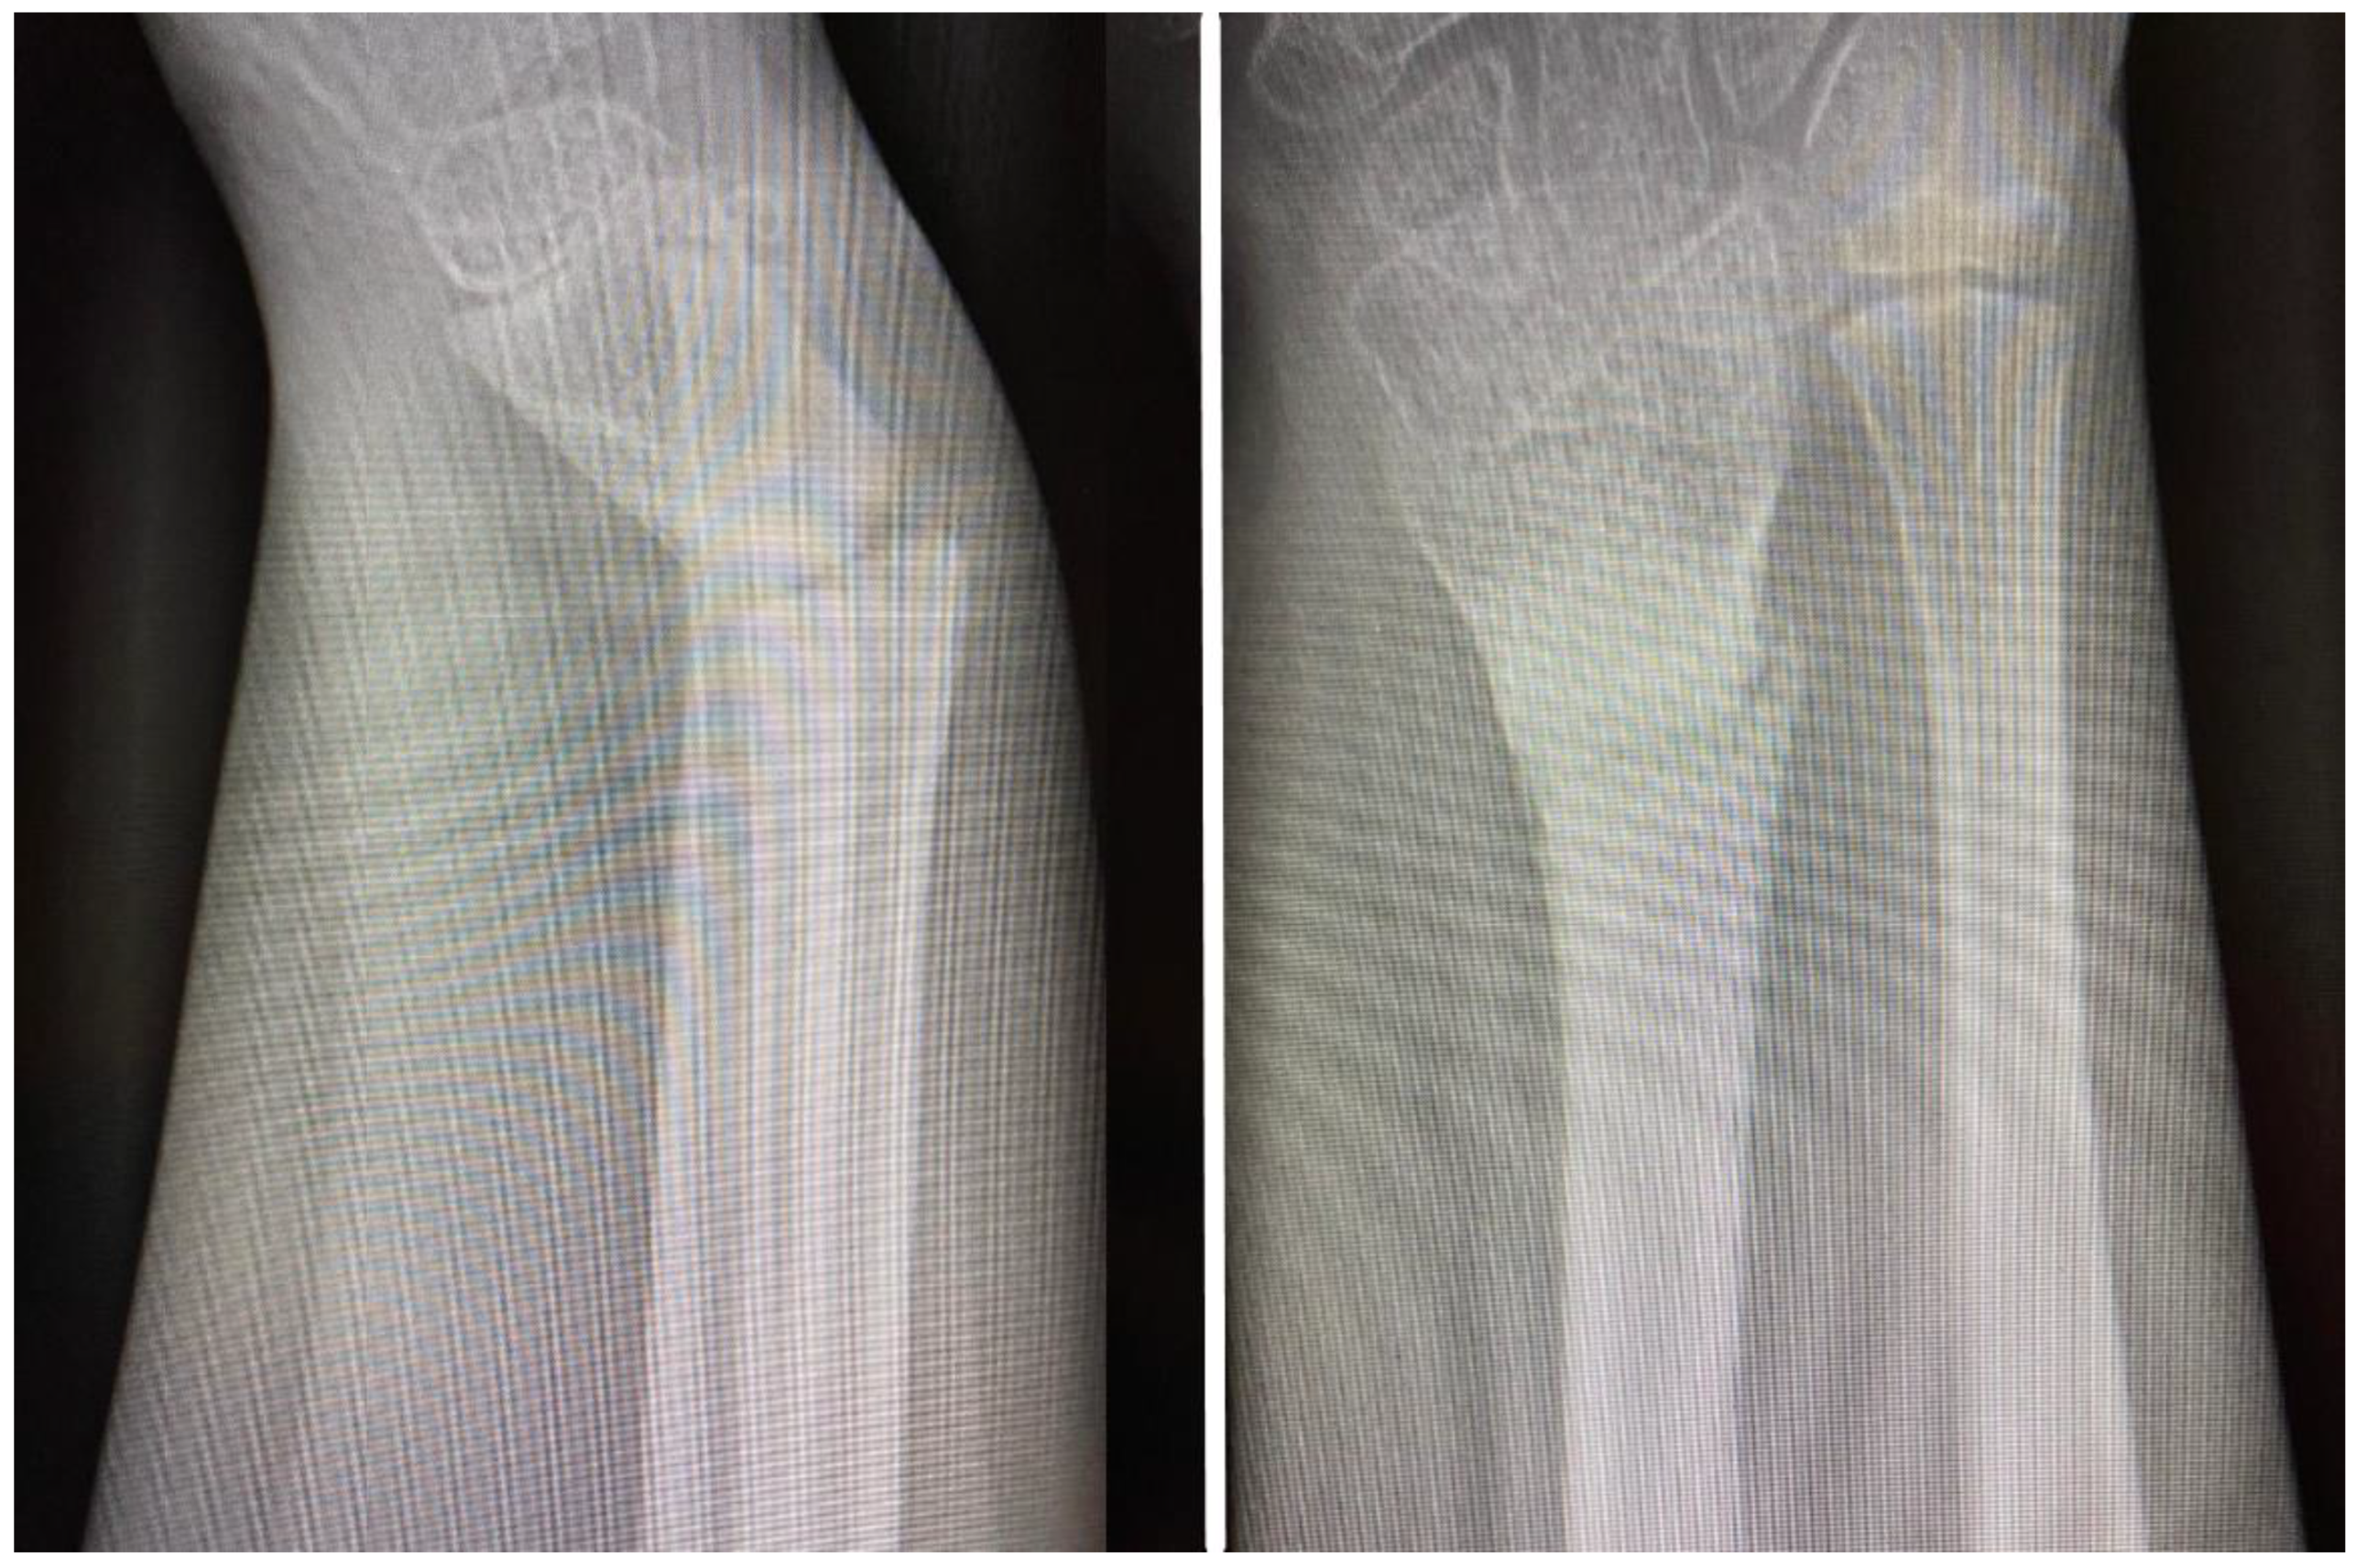

A plain X-ray at initial presentation confirmed a fracture of the distal third of the radius with important displacement and volar angulation >30° (Figure 1A). At presentation, orthopedic reduction was the first gesture but this failed by orthopedic means with a non-successful conservative attempt.

Figure 1. Radiological images obtained at presentation: AP (antero-posterior) (A) and oblique (B) view of the distal forearm, demonstrating important volar displacement of the radial fracture, and greenstick fracture of the distal ulna with dorsal angulation. Also, the fracture presented with a rotational displacement of the distal radial fragment together with the radiocarpal complex.